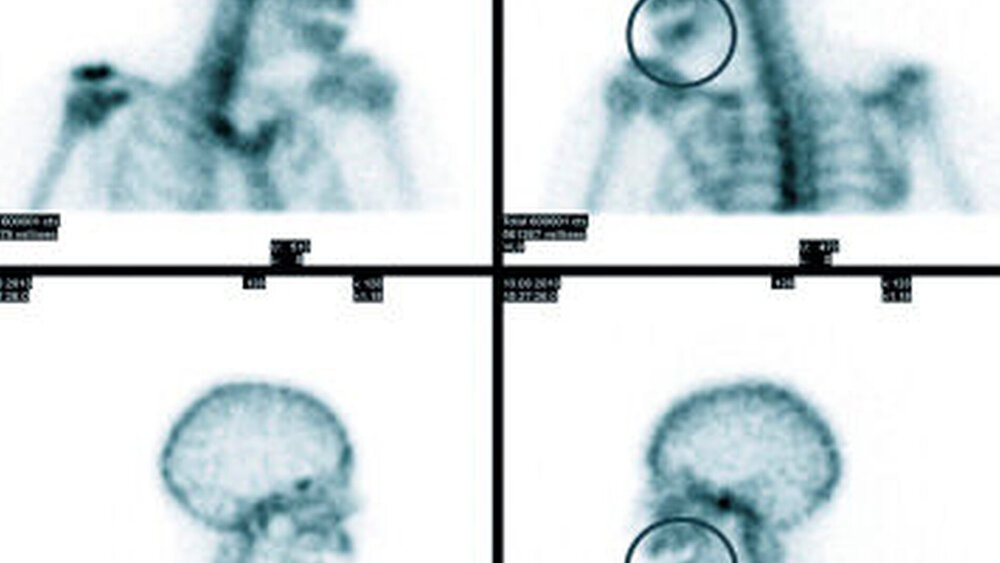

Dreiphasen-Szintigrafie: Die planare Dreiphasen-Szintigrafie mit 99m Tc-markierten Bisphosphonaten ist ein nuklearmedizinisches Standardverfahren in der Diagnose der Kieferosteomyelitis/-nekrose. Sie zeigt die Lokalisation von vermehrtem Knochenumbau (Osteoblastenaktivität) mit hoher Sensitivität an (Abbildung 6). Das Verfahren ist jedoch nicht spezifisch und hat nur eine begrenzte Ortsauflösung [Stockmann et al., 2010].

SPECT(single photon emission computed tomography)-Technik: Die diagnostische Akkuratesse der Szintigrafie kann durch Verwendung der SPECT gesteigert werden (Abbildung 2) [Dore et al., 2009]. Hier werden anders als in der Szintigrafie (in der Aufnahmen aus ventraler und dorsaler Projektion aufgenommen werden) mehrere Aufnahmen aus unterschiedlichen Winkeln akquiriert, aus denen ein dreidimensionales Bild errechnet wird. Dies verbessert die Detektion und die örtliche Zuordnung von fokal vermehrten Traceranreicherungen im Vergleich zu Szintigrafie oder CT allein [Bolouri et al., 2013].

18FDG-PET (18-Fluordeoxy-Glucose): Die Identifikation einer lokalen Entzündung mittels 18FDG-PET beruht darauf, dass aktivierte Granulozyten und Makrophagen Glucose als Energiequelle verwenden. Bei einer entzündungsinduzierten Aktivierung kommt es in diesen Zellen zu einer erhöhten Anreicherung der radioaktiv markierten Glucose [Artiko, 2012]. Die FDG-PET hat sich in der Diagnostik der Osteomyelitis in Studien der vergangenen Jahre als vielversprechende Methode erwiesen [Artiko, 2012; Hartmann et al., 2007; Strobel Stumpe, 2007].

Die PET-CT kombiniert die Stoffwechseldaten mit anatomischer Information aus der CT. Sie bietet eine hohe Ortsauflösung und erlaubt eine Unterscheidung zwischen einer rein auf den Knochen begrenzten Inflammation und einer Infektion der benachbarten Weichteile.